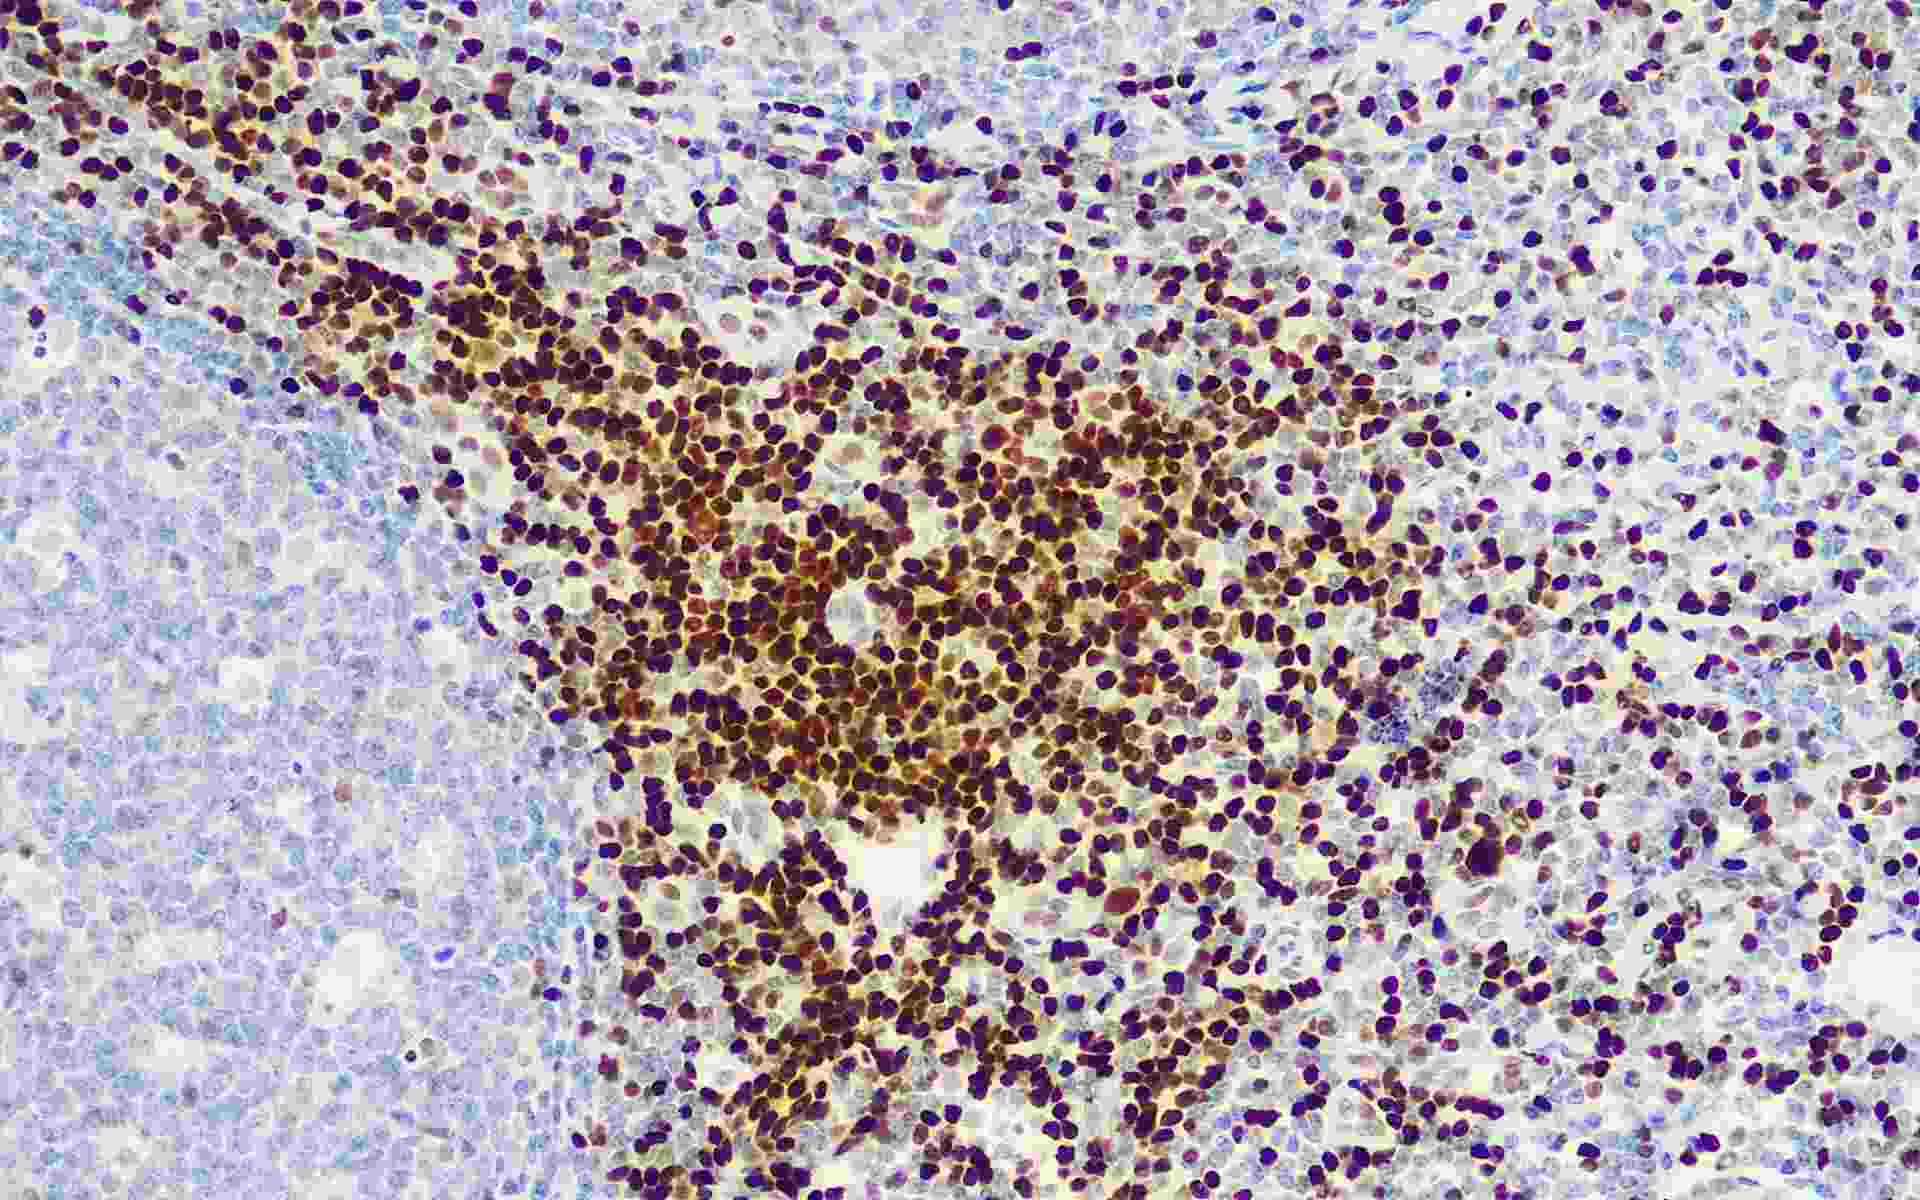

• LEF-1扁桃体

• 染色定位 : 细胞核

• 阳性对照 : 扁桃体